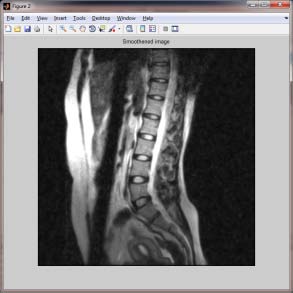

The segmentation of IVD is a prerequisite for the Computer Aided Diagnosis (CAD) of disc degeneration, while it could also be useful for computer based planning prior to spinal surgery [12]. In T2-weighted sagittal MR images a normal disc appears like a bright ellipse because it contain more water content surrounded by a dark ring, whereas a degenerated disc appears darker and often has an irregular shape. These case are shown in fig 1. These features are used in Machine Learning techniques that have been widely and successfully used in CAD [13][14][15]. A novel method is proposed in this paper to detect disc degeneration, disc compression. In proposed method, the intensity values of the inter vertebrae, length width values are extracted to create a template. VESTAL [16] extracts the spinal canal from MR image it guides the proposed method to detect the vertebrae and IVD to extract IVD features.Normal image spinal canal appeared as bright and the path near the vertebrae body also continuous having smooth transition. In abnormal case the problematic disc appeared as dark and the spinal canal near this region also appeared as dark.

Figure 1 II.